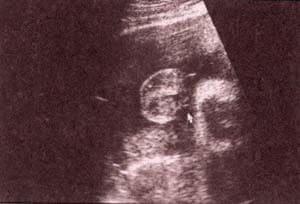

Diagnóstico Prenatal -  genitales externos xx Diagnóstico Prenatal -  genitales externos xx

fig. 49.– (a). genitales externos xx. labios mayores (1) . 32 semanas. fig. 49. – (b). labios menores fusionados (2). 32 semanas.